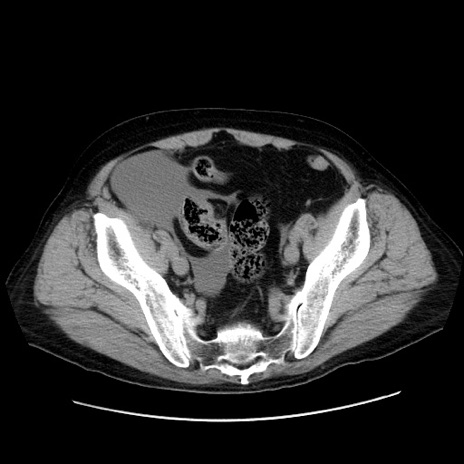

症例30(横断像)

【症例】80歳代男性

【主訴】臍周囲痛

【現病歴】約6時間前から臍下部痛が出現。次第に腹部膨隆・背部痛も生じてきたため来院。背部痛の場所は変化しない。

【身体所見】意識清明、BT 36.3℃、BP  131/87mmHg、P 87bpm、SpO2 100%(RA)、臍周囲自発痛・圧痛あり、反跳痛なし、自発痛部位に一致して板状硬あり、腹部膨隆、腸雑音減弱、CVA tenderness両側陰性。